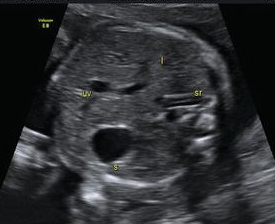

You are looking at the cross-section of fetal abdomen. Looking clockwise, you see spine, stomach, umbilical portion of portal vein. This fetus is?

Vertex